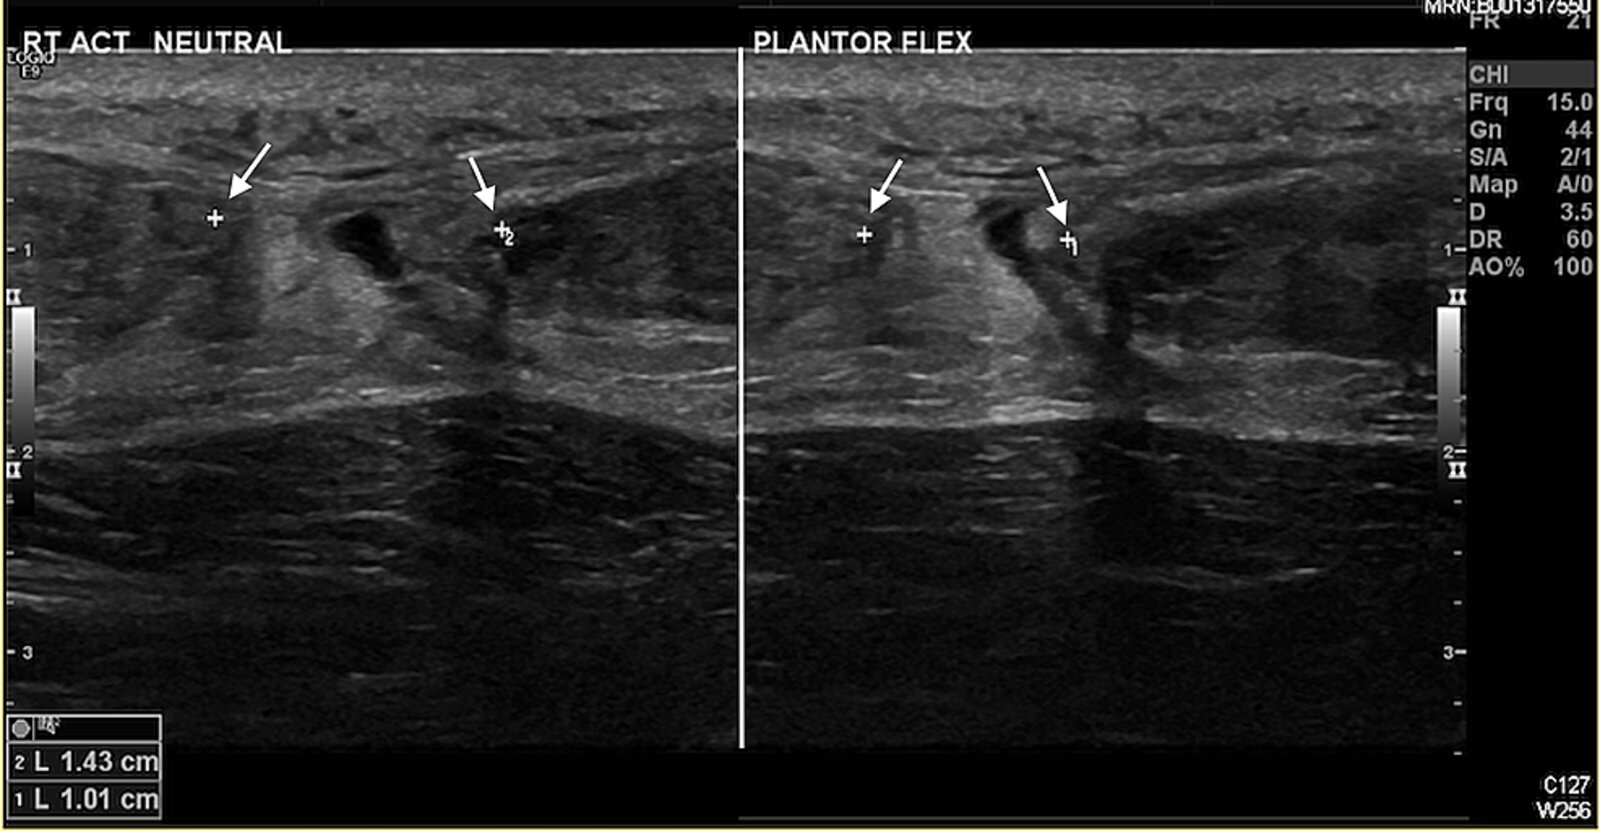

• Confirmatory studies: ultrasound and/or MRI

• Can distinguish partial- and full-thickness tears

• Ultrasound findings include hypoechoic gaps between torn tendon fibers and/or hyperechoic hematoma.